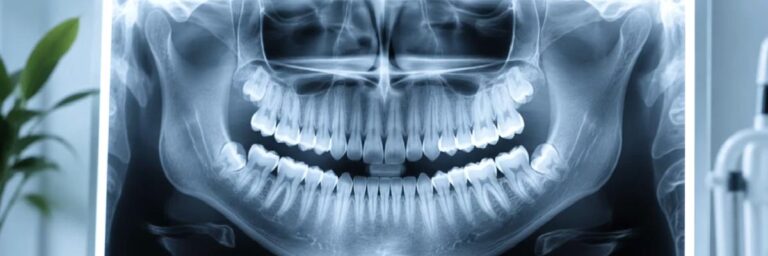

Panoramik röntgen, diş hekimliğinde ağız, dişler ve çene yapısının tek bir görüntüde değerlendirilmesini sağlayan önemli bir görüntüleme yöntemidir. Özellikle ilk muayenelerde, hastanın genel ağız sağlığını hızlı ve kapsamlı şekilde analiz edebilmek için sıklıkla tercih edilir.

Bu görüntüleme sayesinde sadece görünen dişler değil, aynı zamanda gömülü dişler, kemik yapısı ve çene eklemleri de detaylı olarak incelenebilir. Böylece henüz belirti vermemiş problemler erken dönemde tespit edilebilir ve daha büyük sorunların önüne geçilebilir.

Panoramik röntgenin en önemli avantajlarından biri, kısa sürede geniş bir alanı değerlendirme imkanı sunmasıdır. Geleneksel tek diş filmlerine göre daha kapsamlı bir bakış açısı sağlar. Özellikle implant planlaması, ortodontik tedaviler ve cerrahi işlemler öncesinde doğru teşhis için kritik rol oynar.

Tedavi planlamasında doğru teşhis büyük önem taşır. Sadece gözle yapılan muayene bazı durumlarda yeterli olmayabilir. Panoramik röntgen, dişlerin kök yapısını, kemik seviyelerini ve olası patolojileri ortaya koyarak hekime daha net bir yol haritası sunar. Bu da tedavinin daha öngörülebilir ve başarılı olmasını sağlar.